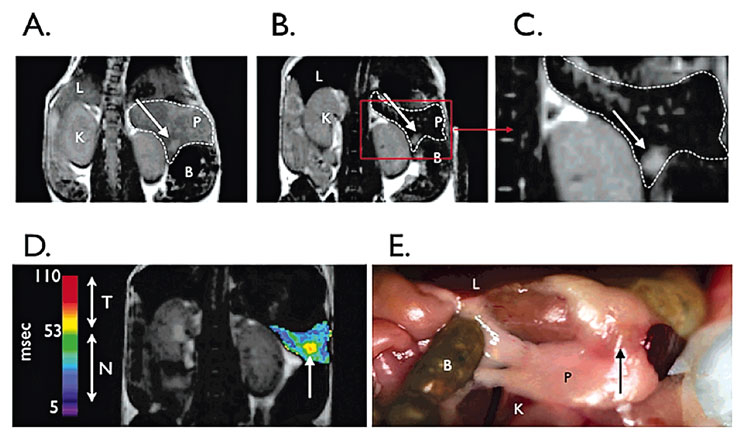

Figure 3

Magnetic resonance imaging (MRI) on T2-weighted sequences of pancreas and tumour.

Preinjection (A) and postinjection (B) of pancreas and tumour. (C) Image from B at higher magnification. Bombesin-targeted nanoparticles permit tumour (arrows) to be seen. Arrow indicates bulk tumour. (D) Postcontrast agent, colorised T2 map of a pancreas with implanted tumour. Tumour has higher T2s than normal pancreas. Abbreviations: L, liver; P, pancreas; K, kidney; B, bowel. (E) Photograph of partially dissected mouse with pancreas and tumour visible.

Molecular imaging has been applied in a variety of fields, among them oncology where it has been proved to enhance the detection of specific tumours by using over-expressed cellular markers as molecular targets. See figure 3 for an example of pancreas tumour imaging, reprinted with permission from [69].